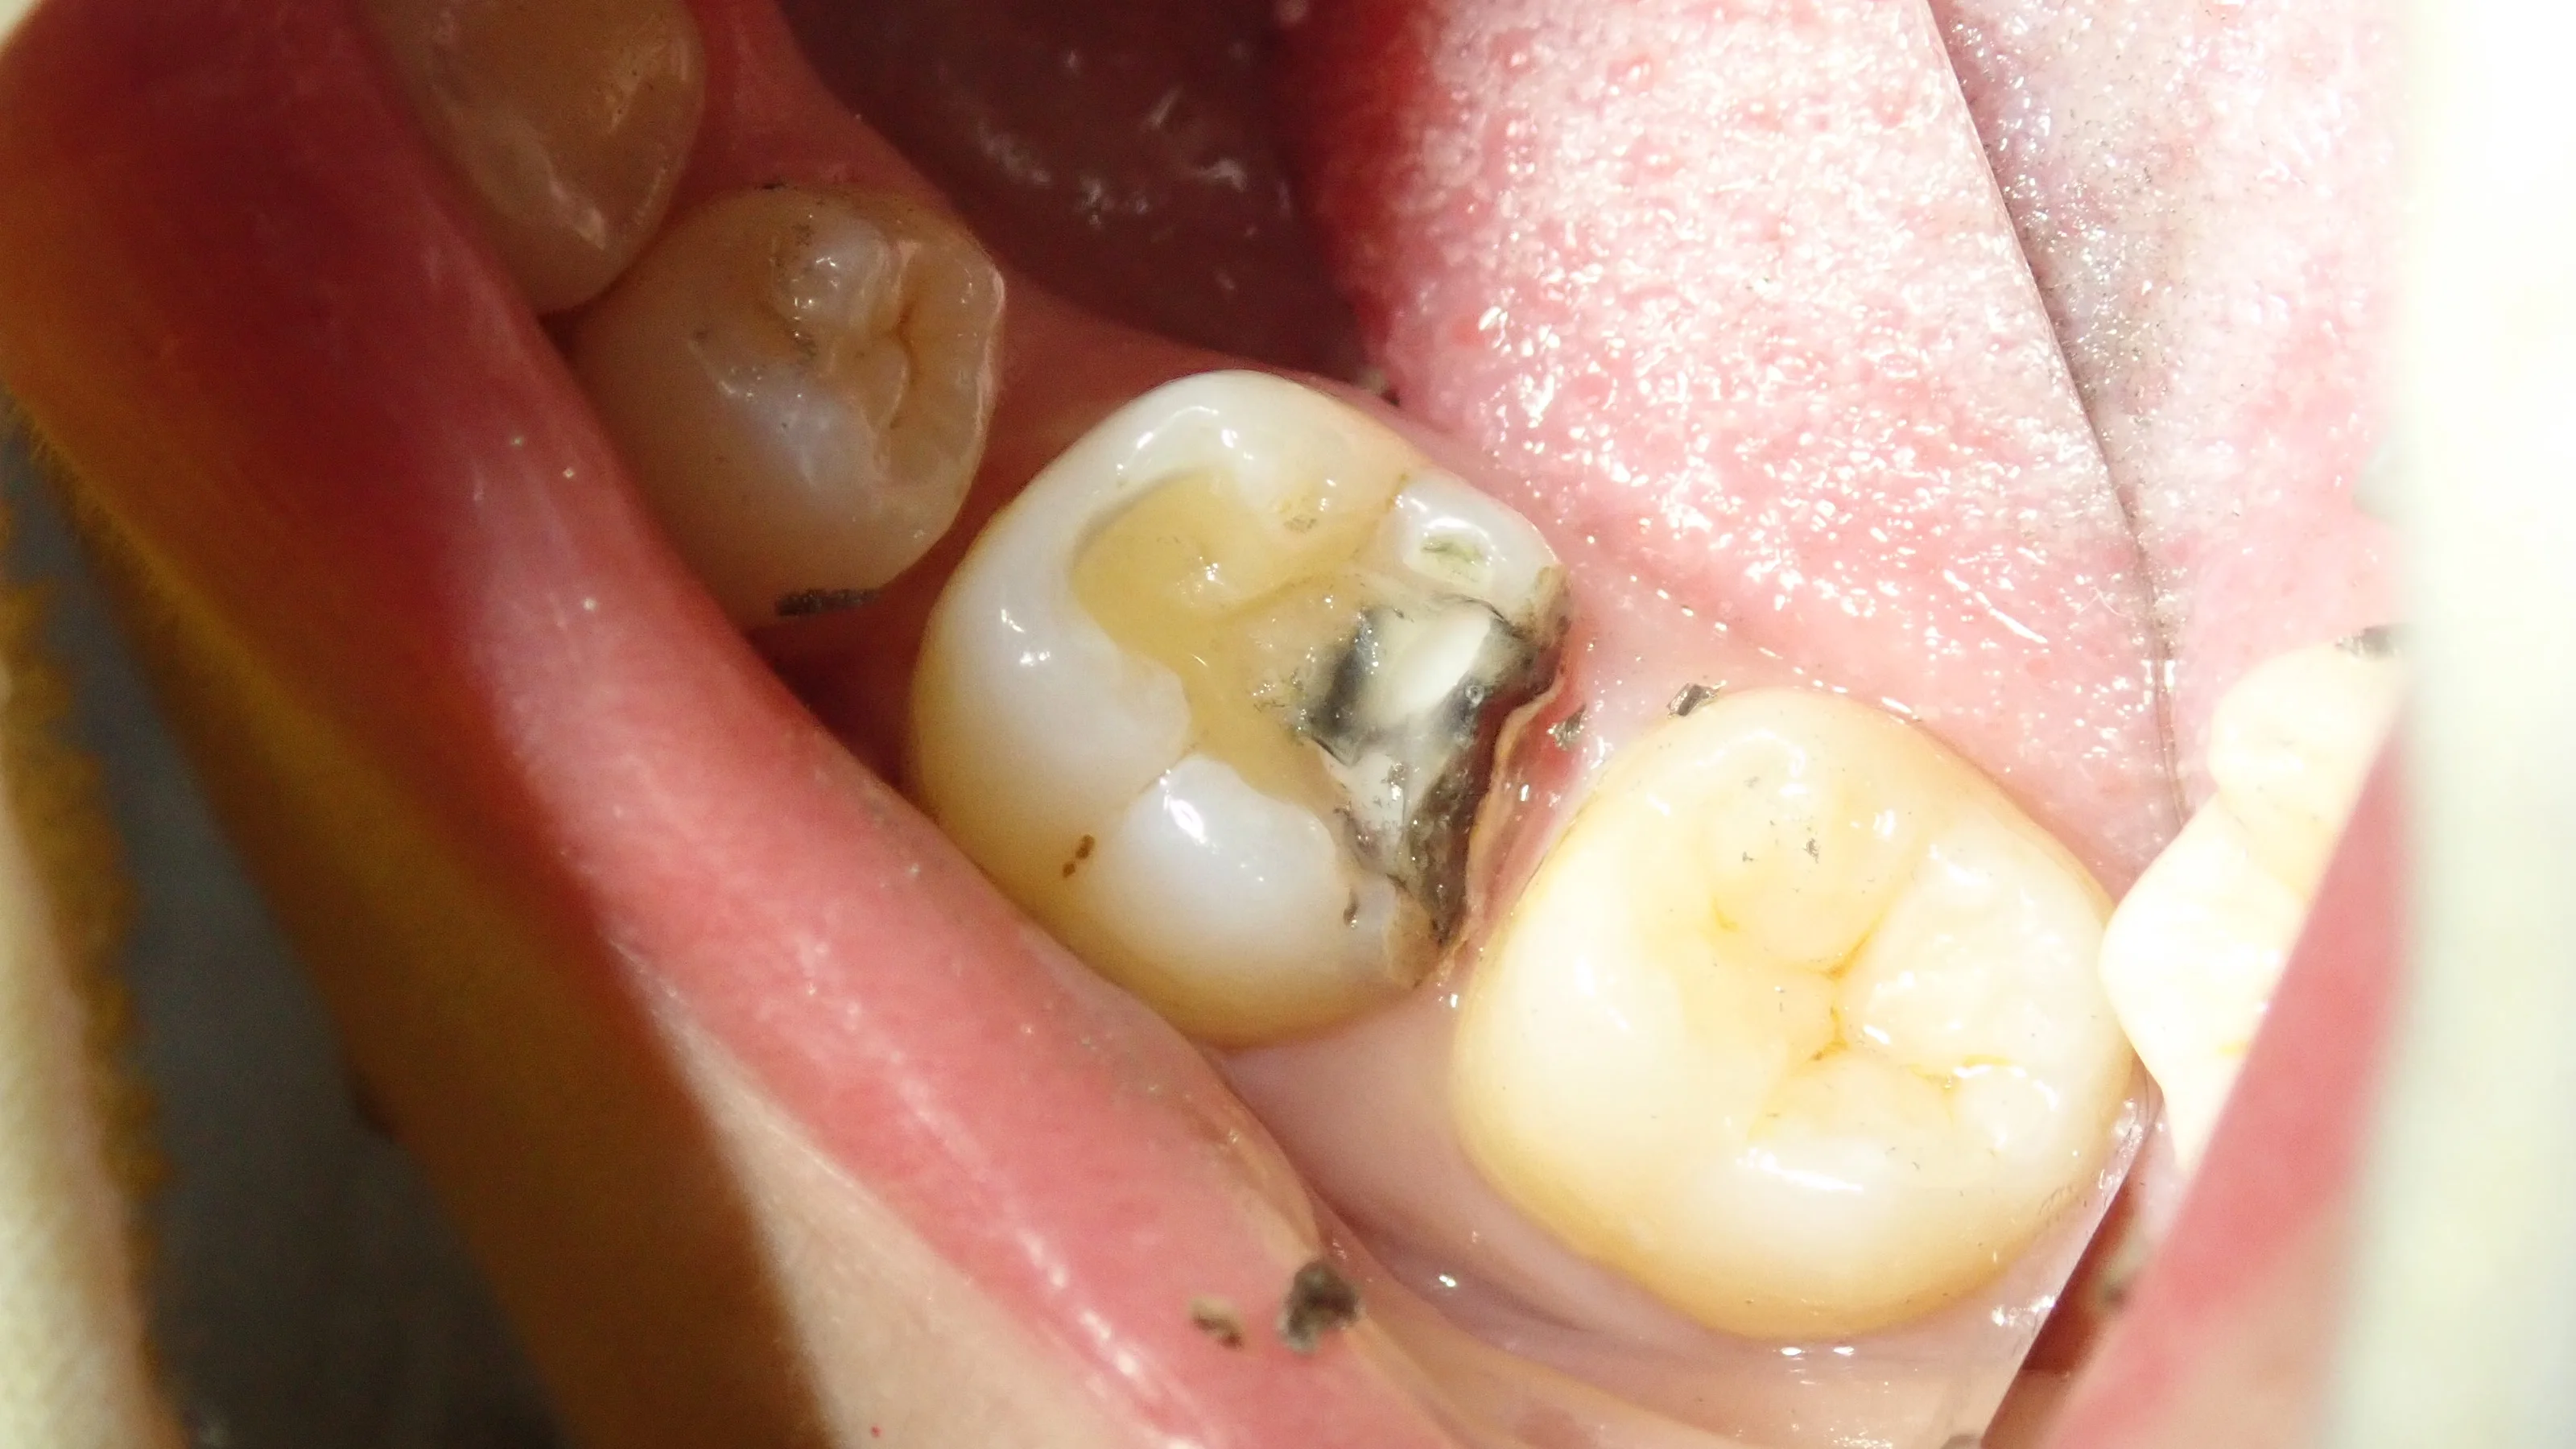

そして別日に症状的には問題なかったため、手前の歯に入りました。

術前がこちら

奥2本のダイレクトボンディング|坂寄歯科医院(取手市藤代) - 画像4

手前の歯との間は矯正の後戻りによって隙間が開いている状況になっています。

金属を軽くとったのがこちらですね。

奥2本のダイレクトボンディング|坂寄歯科医院(取手市藤代) - 画像5

で、完全に虫歯を取り切ったらこうなりました。

奥2本のダイレクトボンディング|坂寄歯科医院(取手市藤代) - 画像6

後ろの歯との間が非常に深くなっています。

手前の歯との間についても、虫歯だったため、歯が少なくなってしまいました。